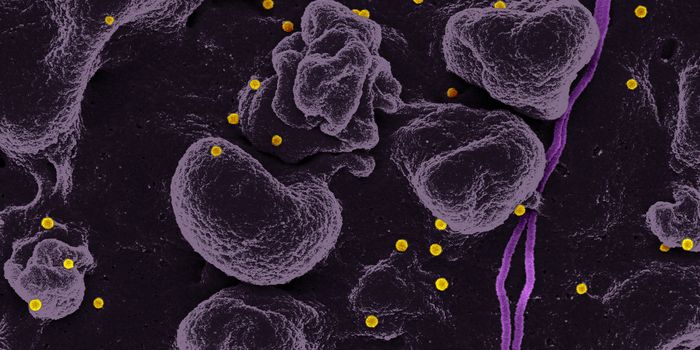

SEP 17, 2021Cell & Molecular BiologyMRSA (methicillin-resistant Staphylococcus aureus) is a well known superbug, a pathogenic microbe that can cause serious ...